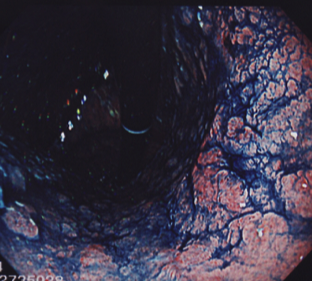

さて、この方は70代の患者様です。

20日間ほど胃もたれが続き、市販薬でも改善しないために胃カメラ検査を受けました。

すると、胃に入ってすぐの部分から広い範囲でややくぼんだで表面が荒れた部分を発見しました。ここからガン細胞が見つかりました。

根の深さは浅そうでしたが、範囲は胃の入り口から胃の中間部分まであり、場合によっては更に広い範囲にまで広がっている可能性もありました。

内視鏡的な切除や噴門側切除など、いろいろと治療法を検討し、最終的に腹腔鏡下胃全摘出術を行うことにしました。